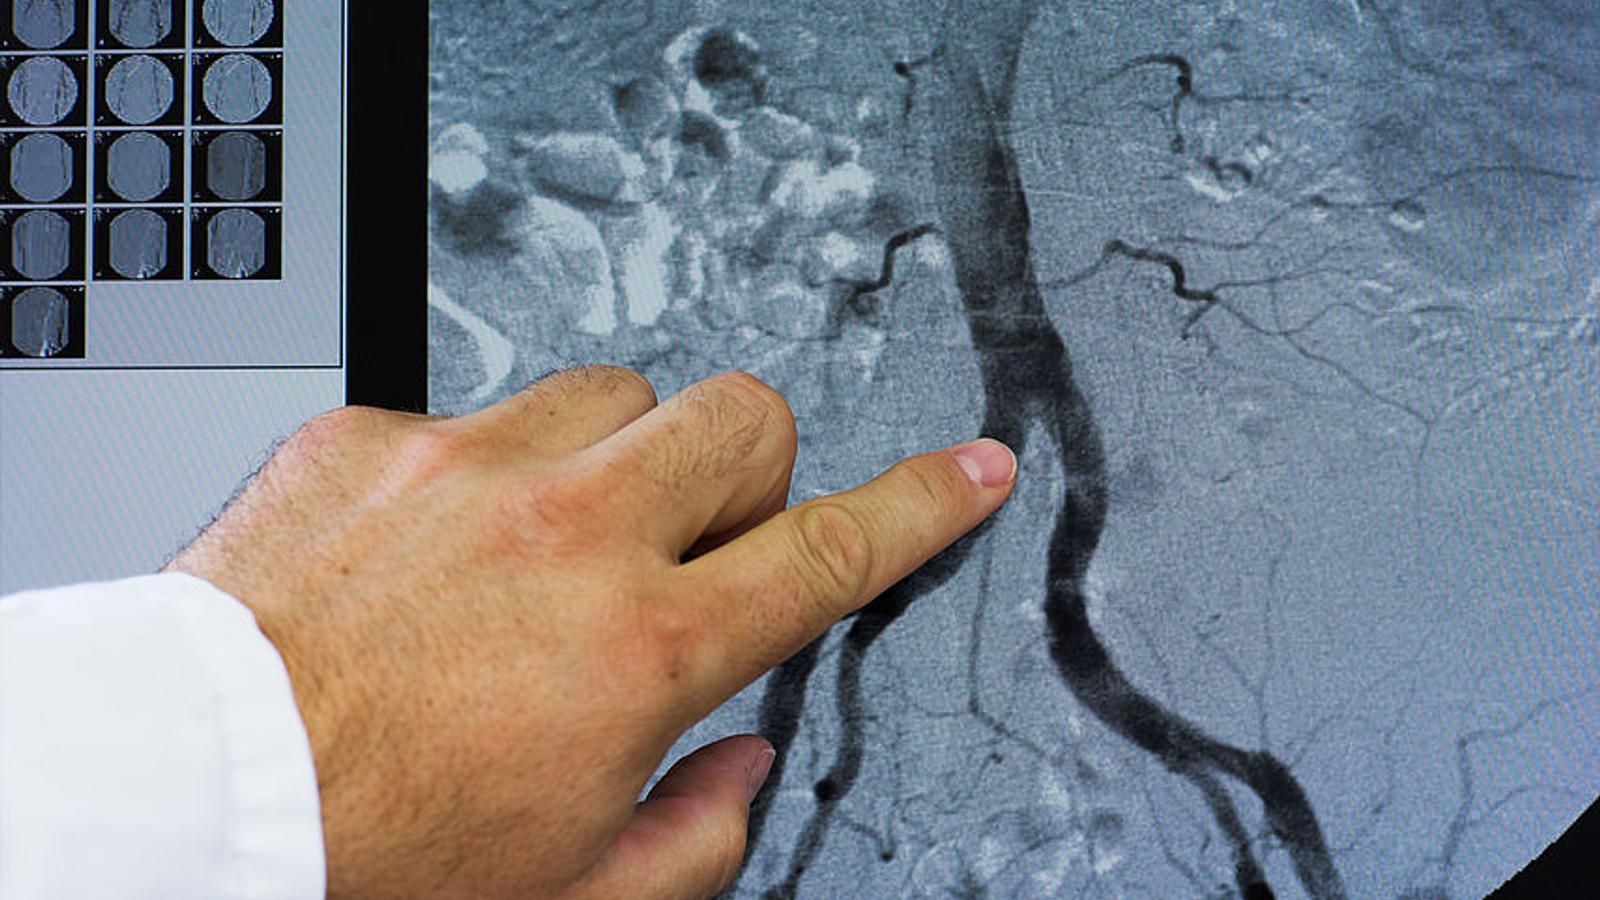

Angiografie einer Vene

Bei der Angiographie können auch therapeutische Eingriffe, wie zum Beispiel das Einsetzen von Stents oder Herzklappen vorgenommen werden.

Die Angiographie ist eine Röntgenuntersuchung mit deren Hilfe Gefäßverschlüsse, Einengungen, Blutungen oder krankhafte atherosklerotische Veränderungen der Gefäße aufgedeckt werden können.

In das Gefäß, das der Arzt untersuchen möchte, wird Kontrastmittel injiziert und mittels Durchleuchtung, digitaler Subtraktionsangiographie (DSA), Magnetresonanztomographie (MRT) oder Computertomographie (CT) sichtbar gemacht. Nur im Rahmen der intraarteriellen Angiographie kann gleichzeitig mit einem Führungsdraht ein Ballonkatheter oder in der Folge ein Stent eingeführt werden, um durch Ballondilatation und Stenting den Blutfluss in einem beschädigten Gefäß zu verbessern. Neben den Arterien (Arteriographie) können mit diesem Untersuchungsverfahren Venen (Phlebographie) oder Lymphgefäße (Lymphographie) bildlich dargestellt werden.